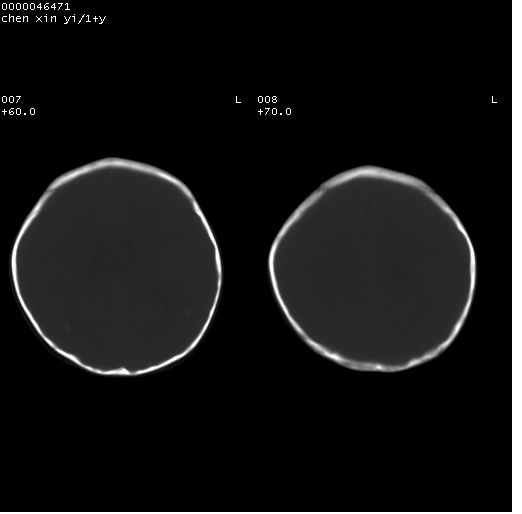

以下是引用zhangzhongshou在2008-4-9 12:54:00的发言:[br]请结合病史,有以下可能1、炎性肉芽肿钙化(含结核)2、寄生虫钙化(含脑囊虫)3、其他良性钙化性病变